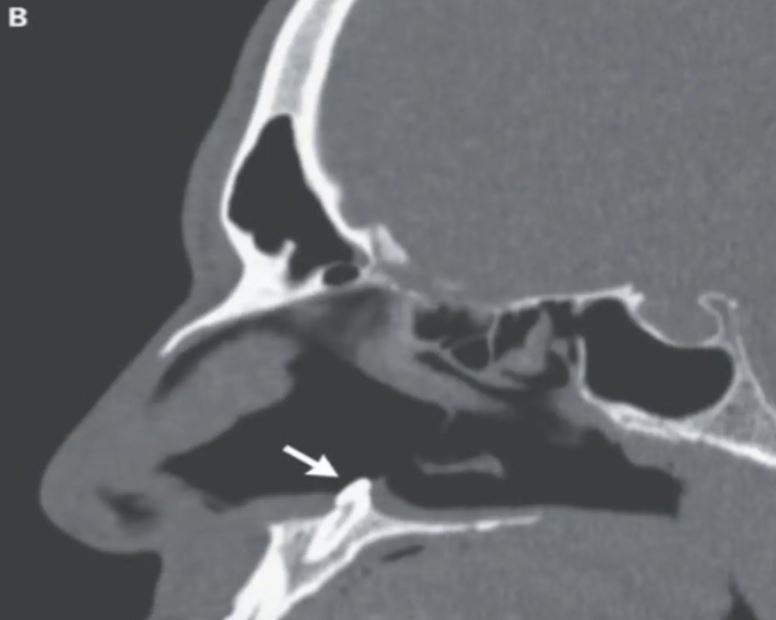

Lelaki itu yang mengunjungi Mount Sinai Health System di New York telah menjalani ujian rinoskopi menggunakan kamera kecil yang dimasukkan ke dalam lubang hidung kanannya.

Hasil pemeriksaan menemui gigi ektopik, iaitu gigi yang tumbuh di tempat tidak normal berukuran sepanjang 15.24 sentimeter.

Penemuan yang dibuat pakar bedah Dr. Sagar Khanna dan Michael Turner ini juga telah diterbitkan dalam New England Journal of Medicine (NEJM).